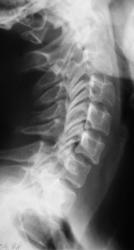

Пациент предъявляет жалобы на боли в плечевом суставе. Направлен на рентгенографию плечевого сустава хирургом. Со стороны плечевого сустава (рентгенограмма) патологических изменений не выявлено. Произведено исследование шейного отдела позвоночника.

Валентин Львович! Не могу посчитать позвонки, перекрываются углом нижней челюсти. Ну то, что имеется остеохондроз, это понятно. Аномалия развития в виде расщепления остистого отростка позвонка или C2 или C3 позвонка. Но откуда у С1 остистый отросток?

Что же касается данной шеи: считаю необходимым дообследования - рентгенография С1 позвонка "через рот", более информативно будет.